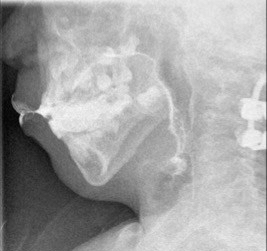

traction et réaction dans le plan sagittal

la traction pré-opératoire avec le halo permet une réduction dans plusieurs plan avent de réaliser la fusion.

traction et ré-axation dans le plan axial

la traction peut être appliquée en pré-opératoire avec le halo, ou en per-opératoire en distractant le montage.

la réduction est modeste mais permet tout de même de corriger l’impression basilaire ; en fait, c’est surtout la suppression de la mobilité par l’arthrodèse qui rend cette impression basilaire inoffensive.